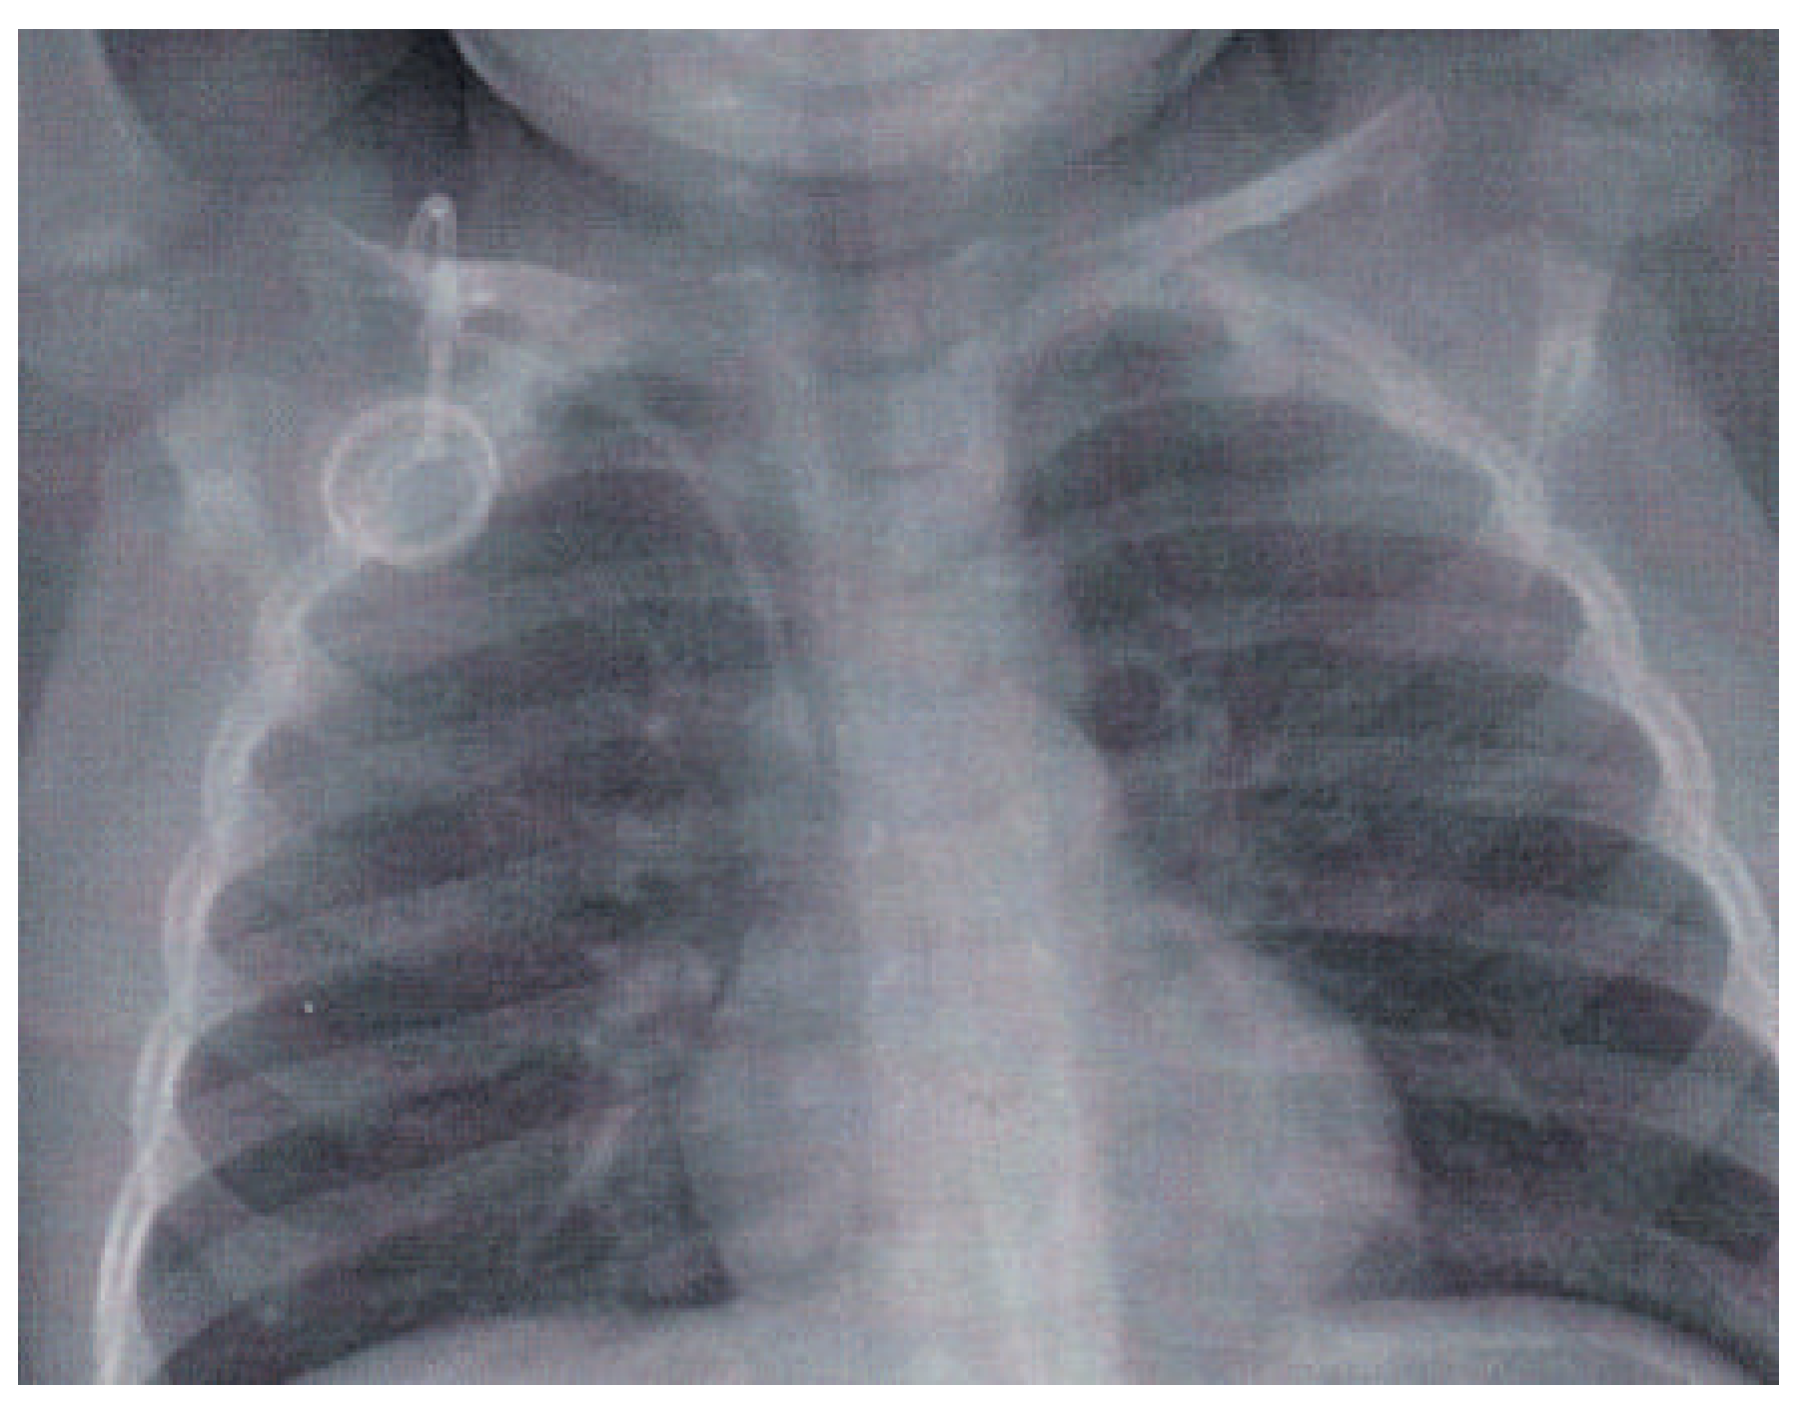

A 2-year-old boy was diagnosed with acute lymphatic leukaemia. For treatment a Port-a-Cath system was implanted surgically in standard fashion via the right subclavian vein (Figure 1).

Figure 1. Chest X-ray immediately after implantation of the Port-a-Cath system showing the correct position of the system with the distal end of the canula in the superior vena cava.